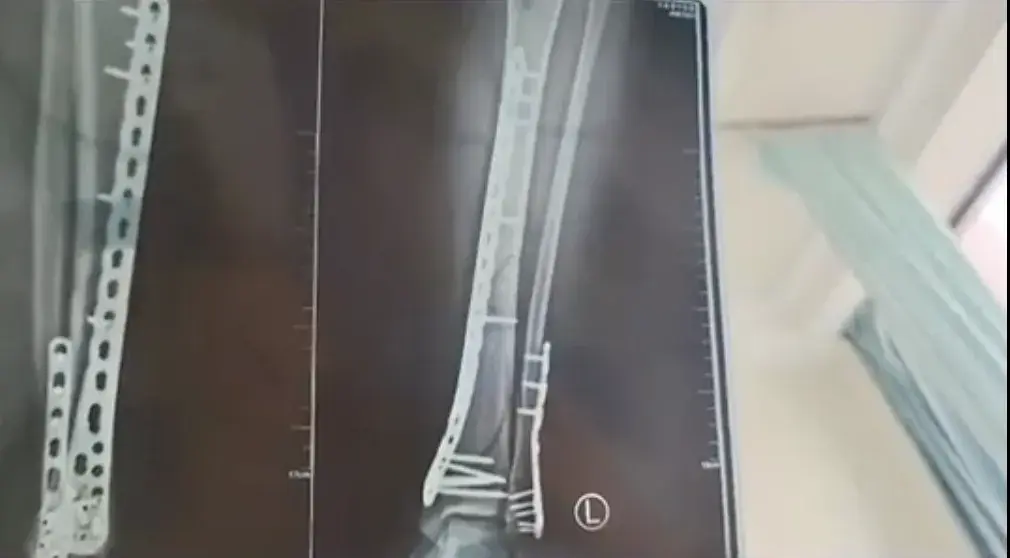

今年6月,甘肃一女子穿7厘米厚底洞洞鞋下楼,崴脚致粉碎性骨折。消息一出,不少网友都表示“怕怕”。